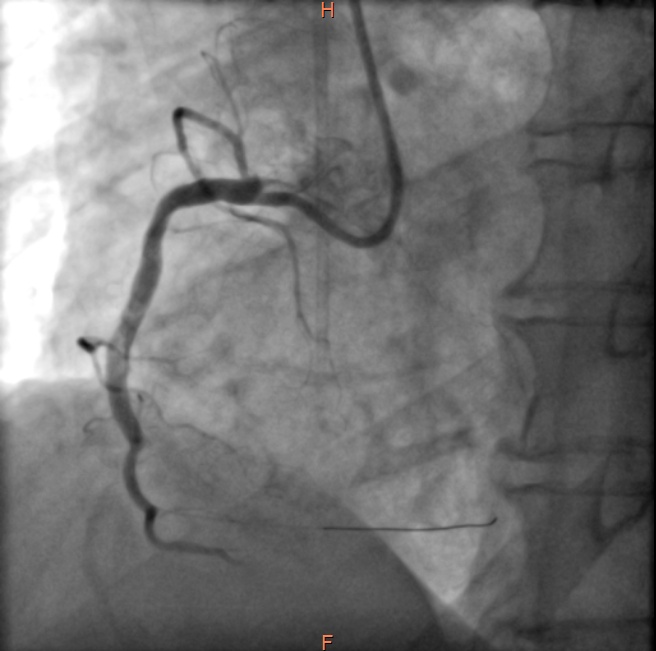

虽然如此,病人右冠状动脉的危险情况仍未完全解除,如同达摩克利斯之剑悬在头顶,不知未来哪天还会再发心肌梗死。经过心内科医师与患者家属的积极沟通解释,几日后再次送至导管室,于右冠状动脉病变处植入了心脏支架,保障了血流通畅。

右冠复查造影